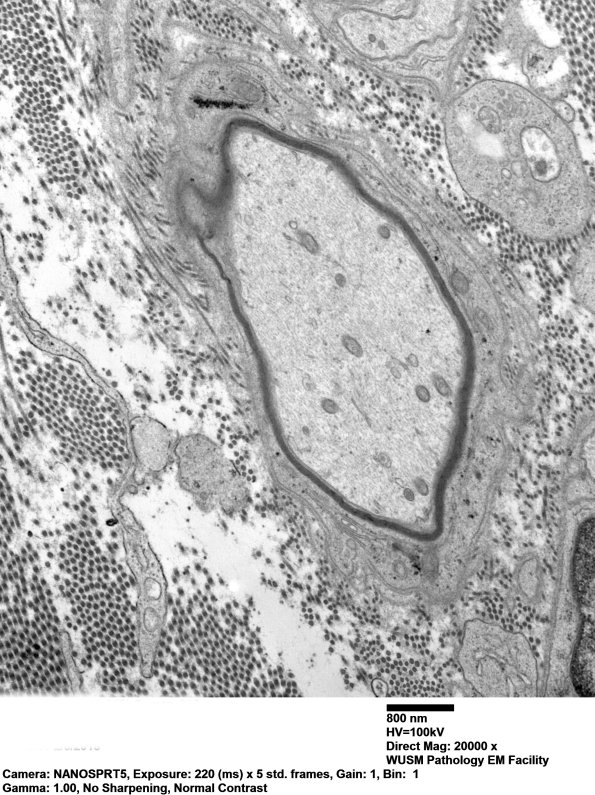

3C2,3 Two other examples of demyelinated axons in this case. (electron micrographs)